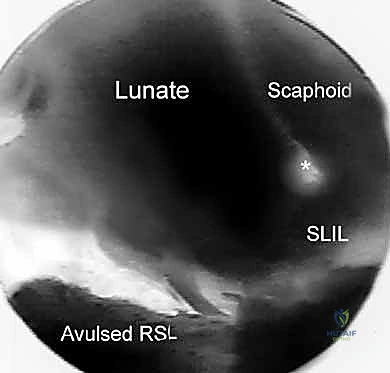

- Function: Indicated for evaluating the dorsal radiocarpal ligament (DRCL) and the palmar portion of the scapholunate interosseous ligament (SLIL). It provides a clear view of dorsal rim fragments for arthroscopic reduction of intra-articular distal radius fractures.